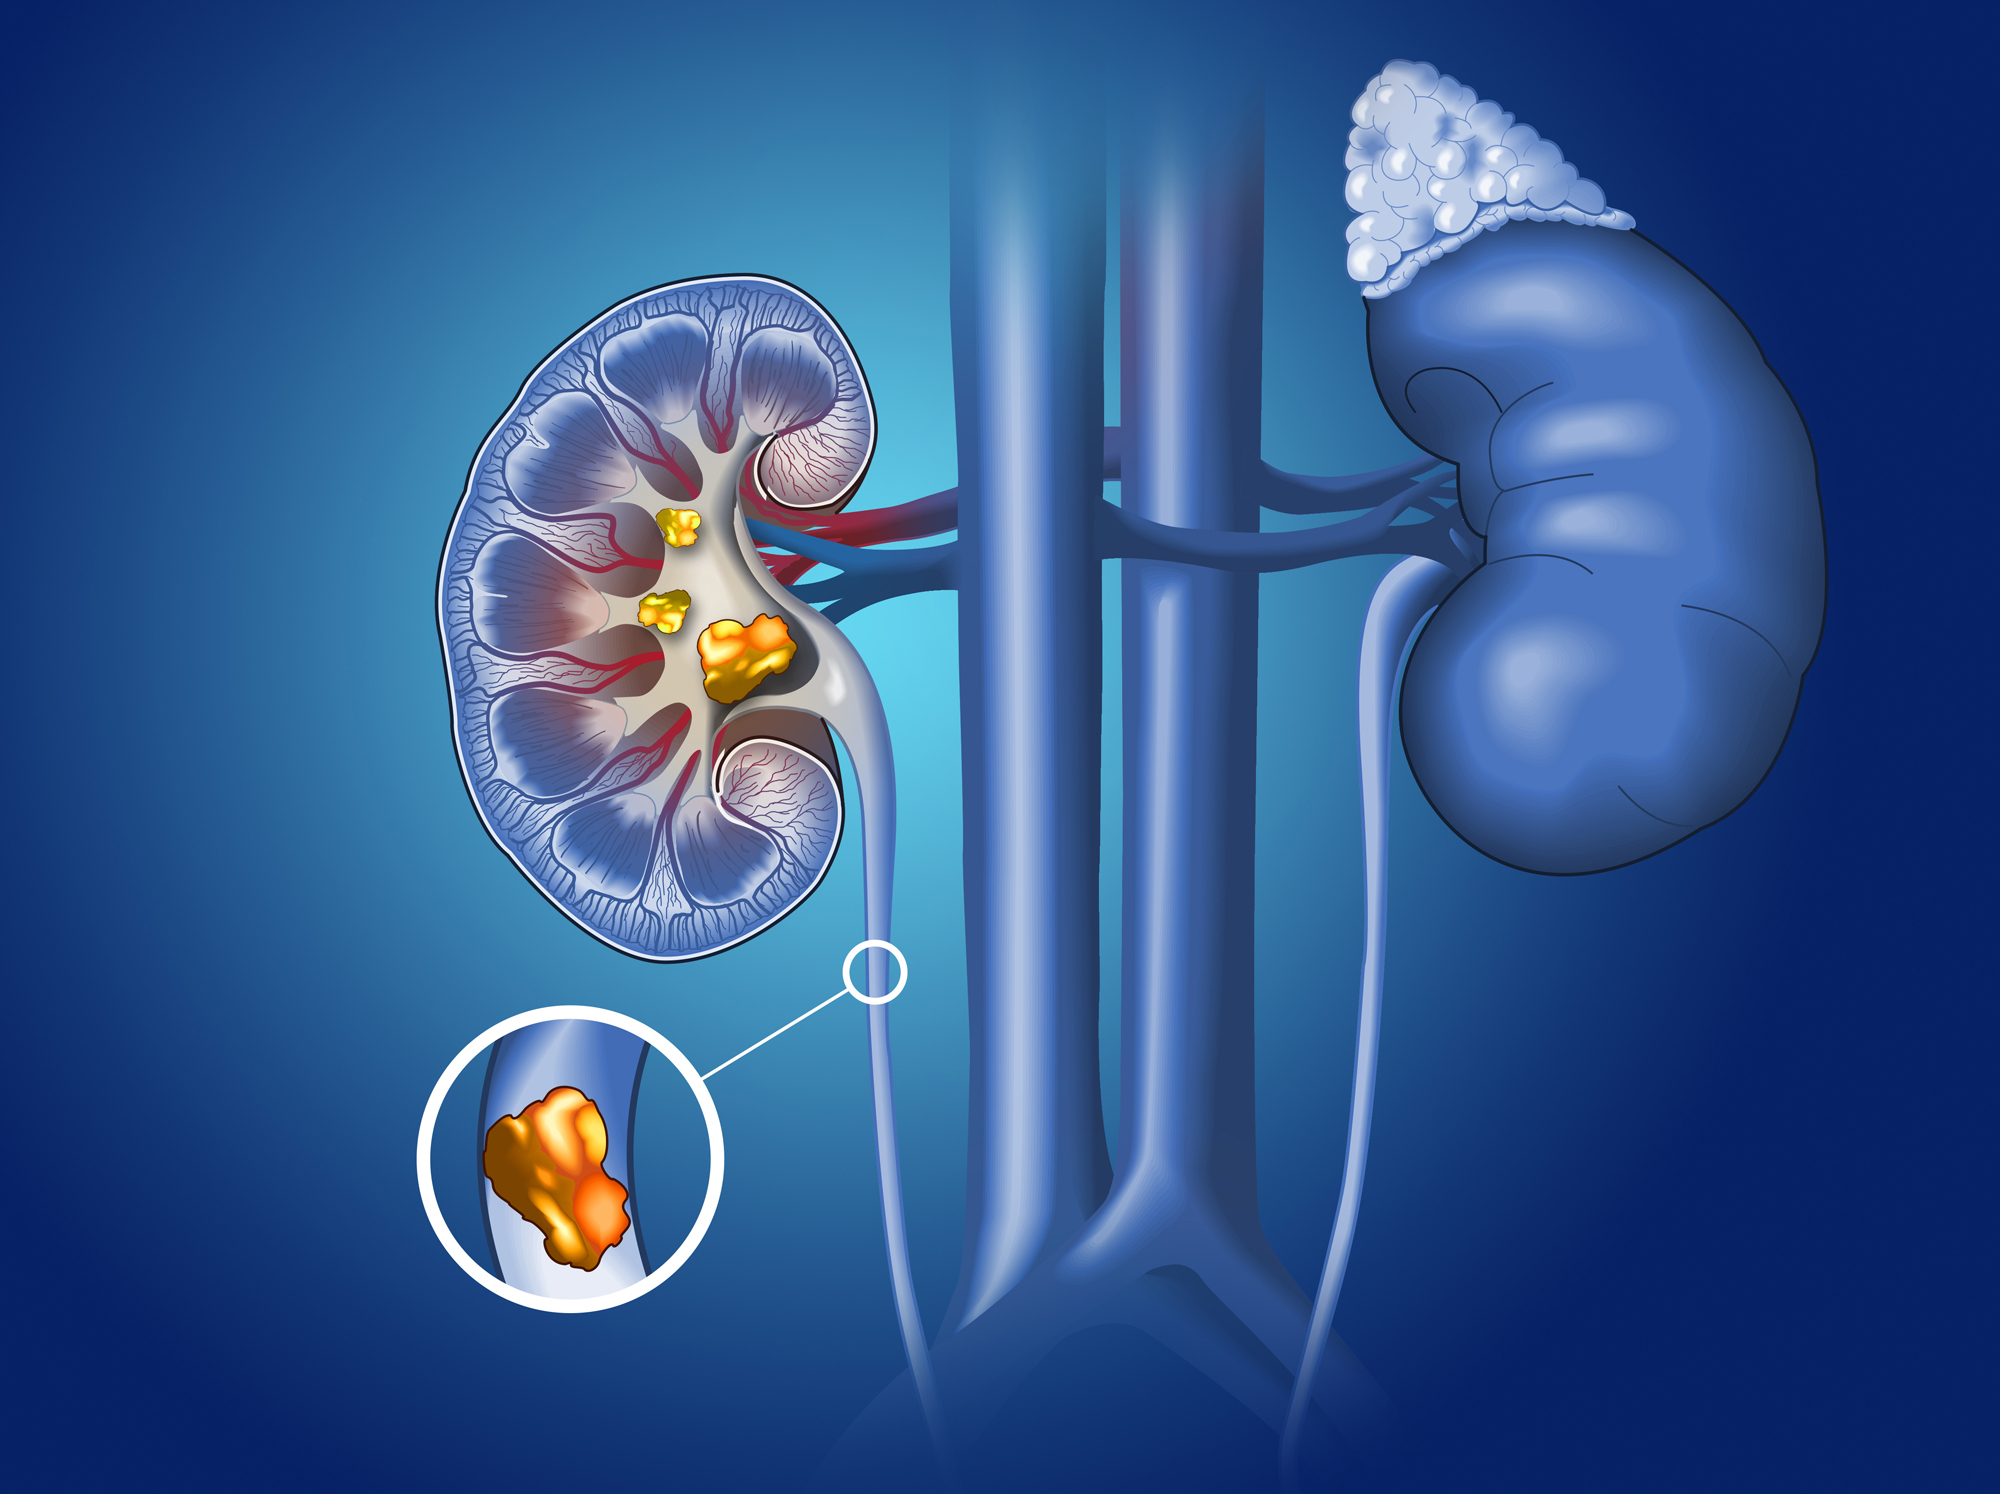

Kidney stones are hard mineral deposits that form inside your kidneys. They cause excruciating pain when they pass through your urinary tract.